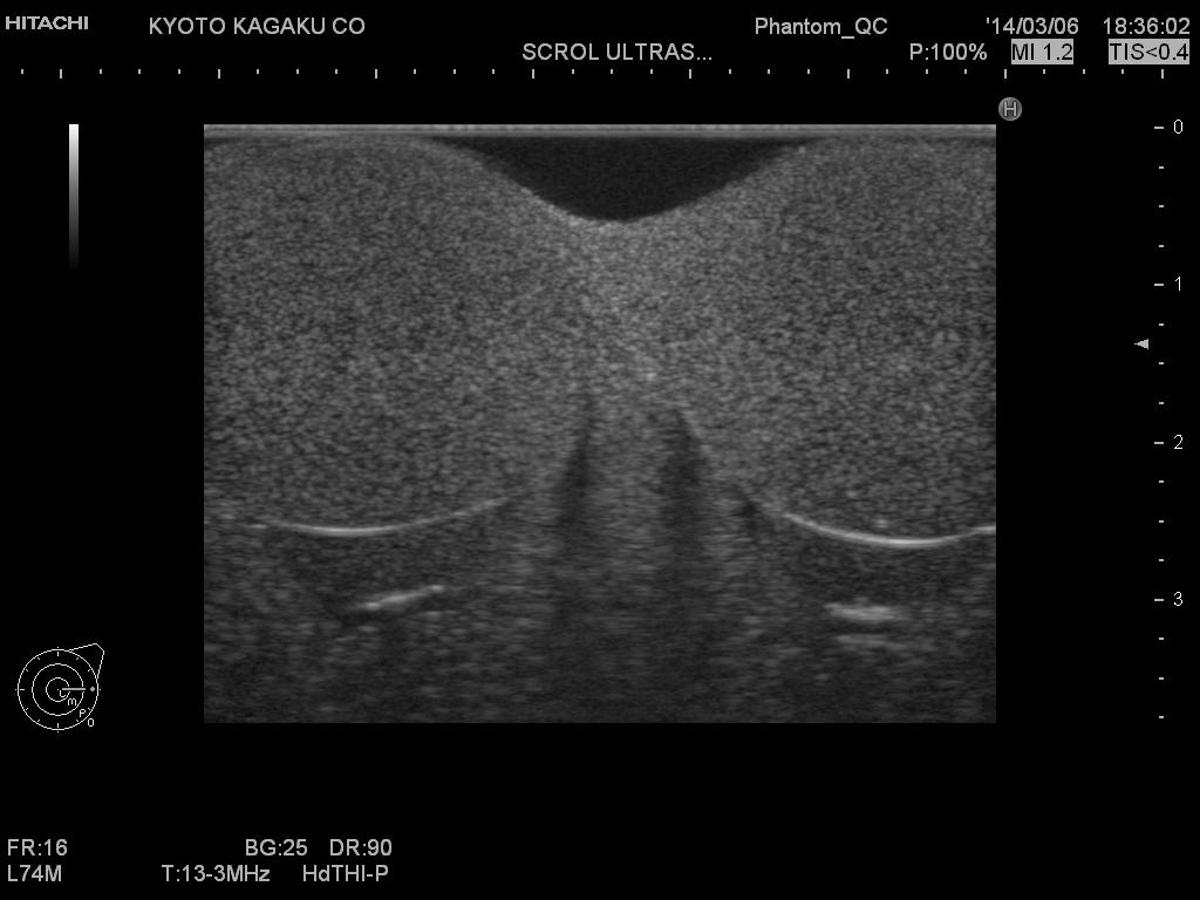

A high-fidelity phantom for teaching and practising scrotal ultrasound procedures and learning to identify abnormalities.